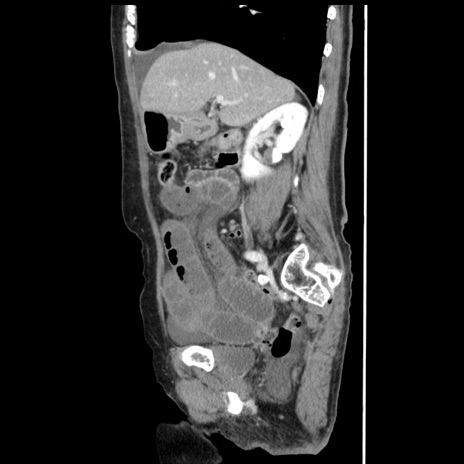

症例1(矢状断像)

【症例】80歳代女性

【主訴】腹痛

【現病歴】8時間前から腹痛あり来院。

【既往歴】糖尿病、脂質異常症、子宮体癌にて子宮全摘術

【身体所見】意識清明・会話良好だが腹痛で苦悶様、全腹部にわたって反跳痛と圧痛あり

【データ】WBC 13600、CRP 0.14、LDH 224、CK 90